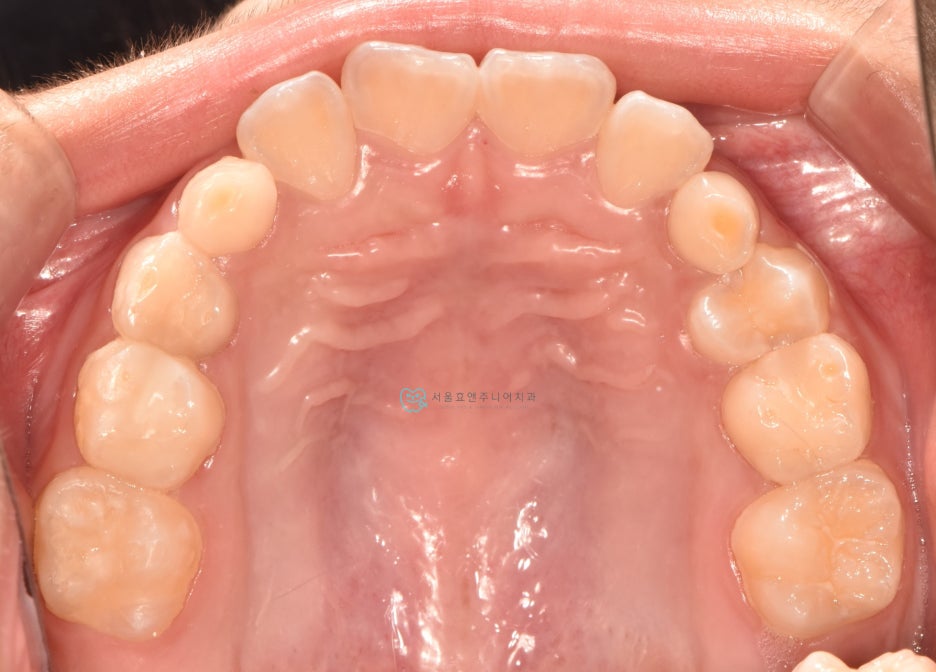

초진사진입니다

초진사진입니다. 11세 5개월 환아로, 반대교합을 보이고 있습니다. 반대교합으로 인해 치아가 부딪혀 치은퇴축(잇몸이 내려감)도 보이고 있네요.(화살표)